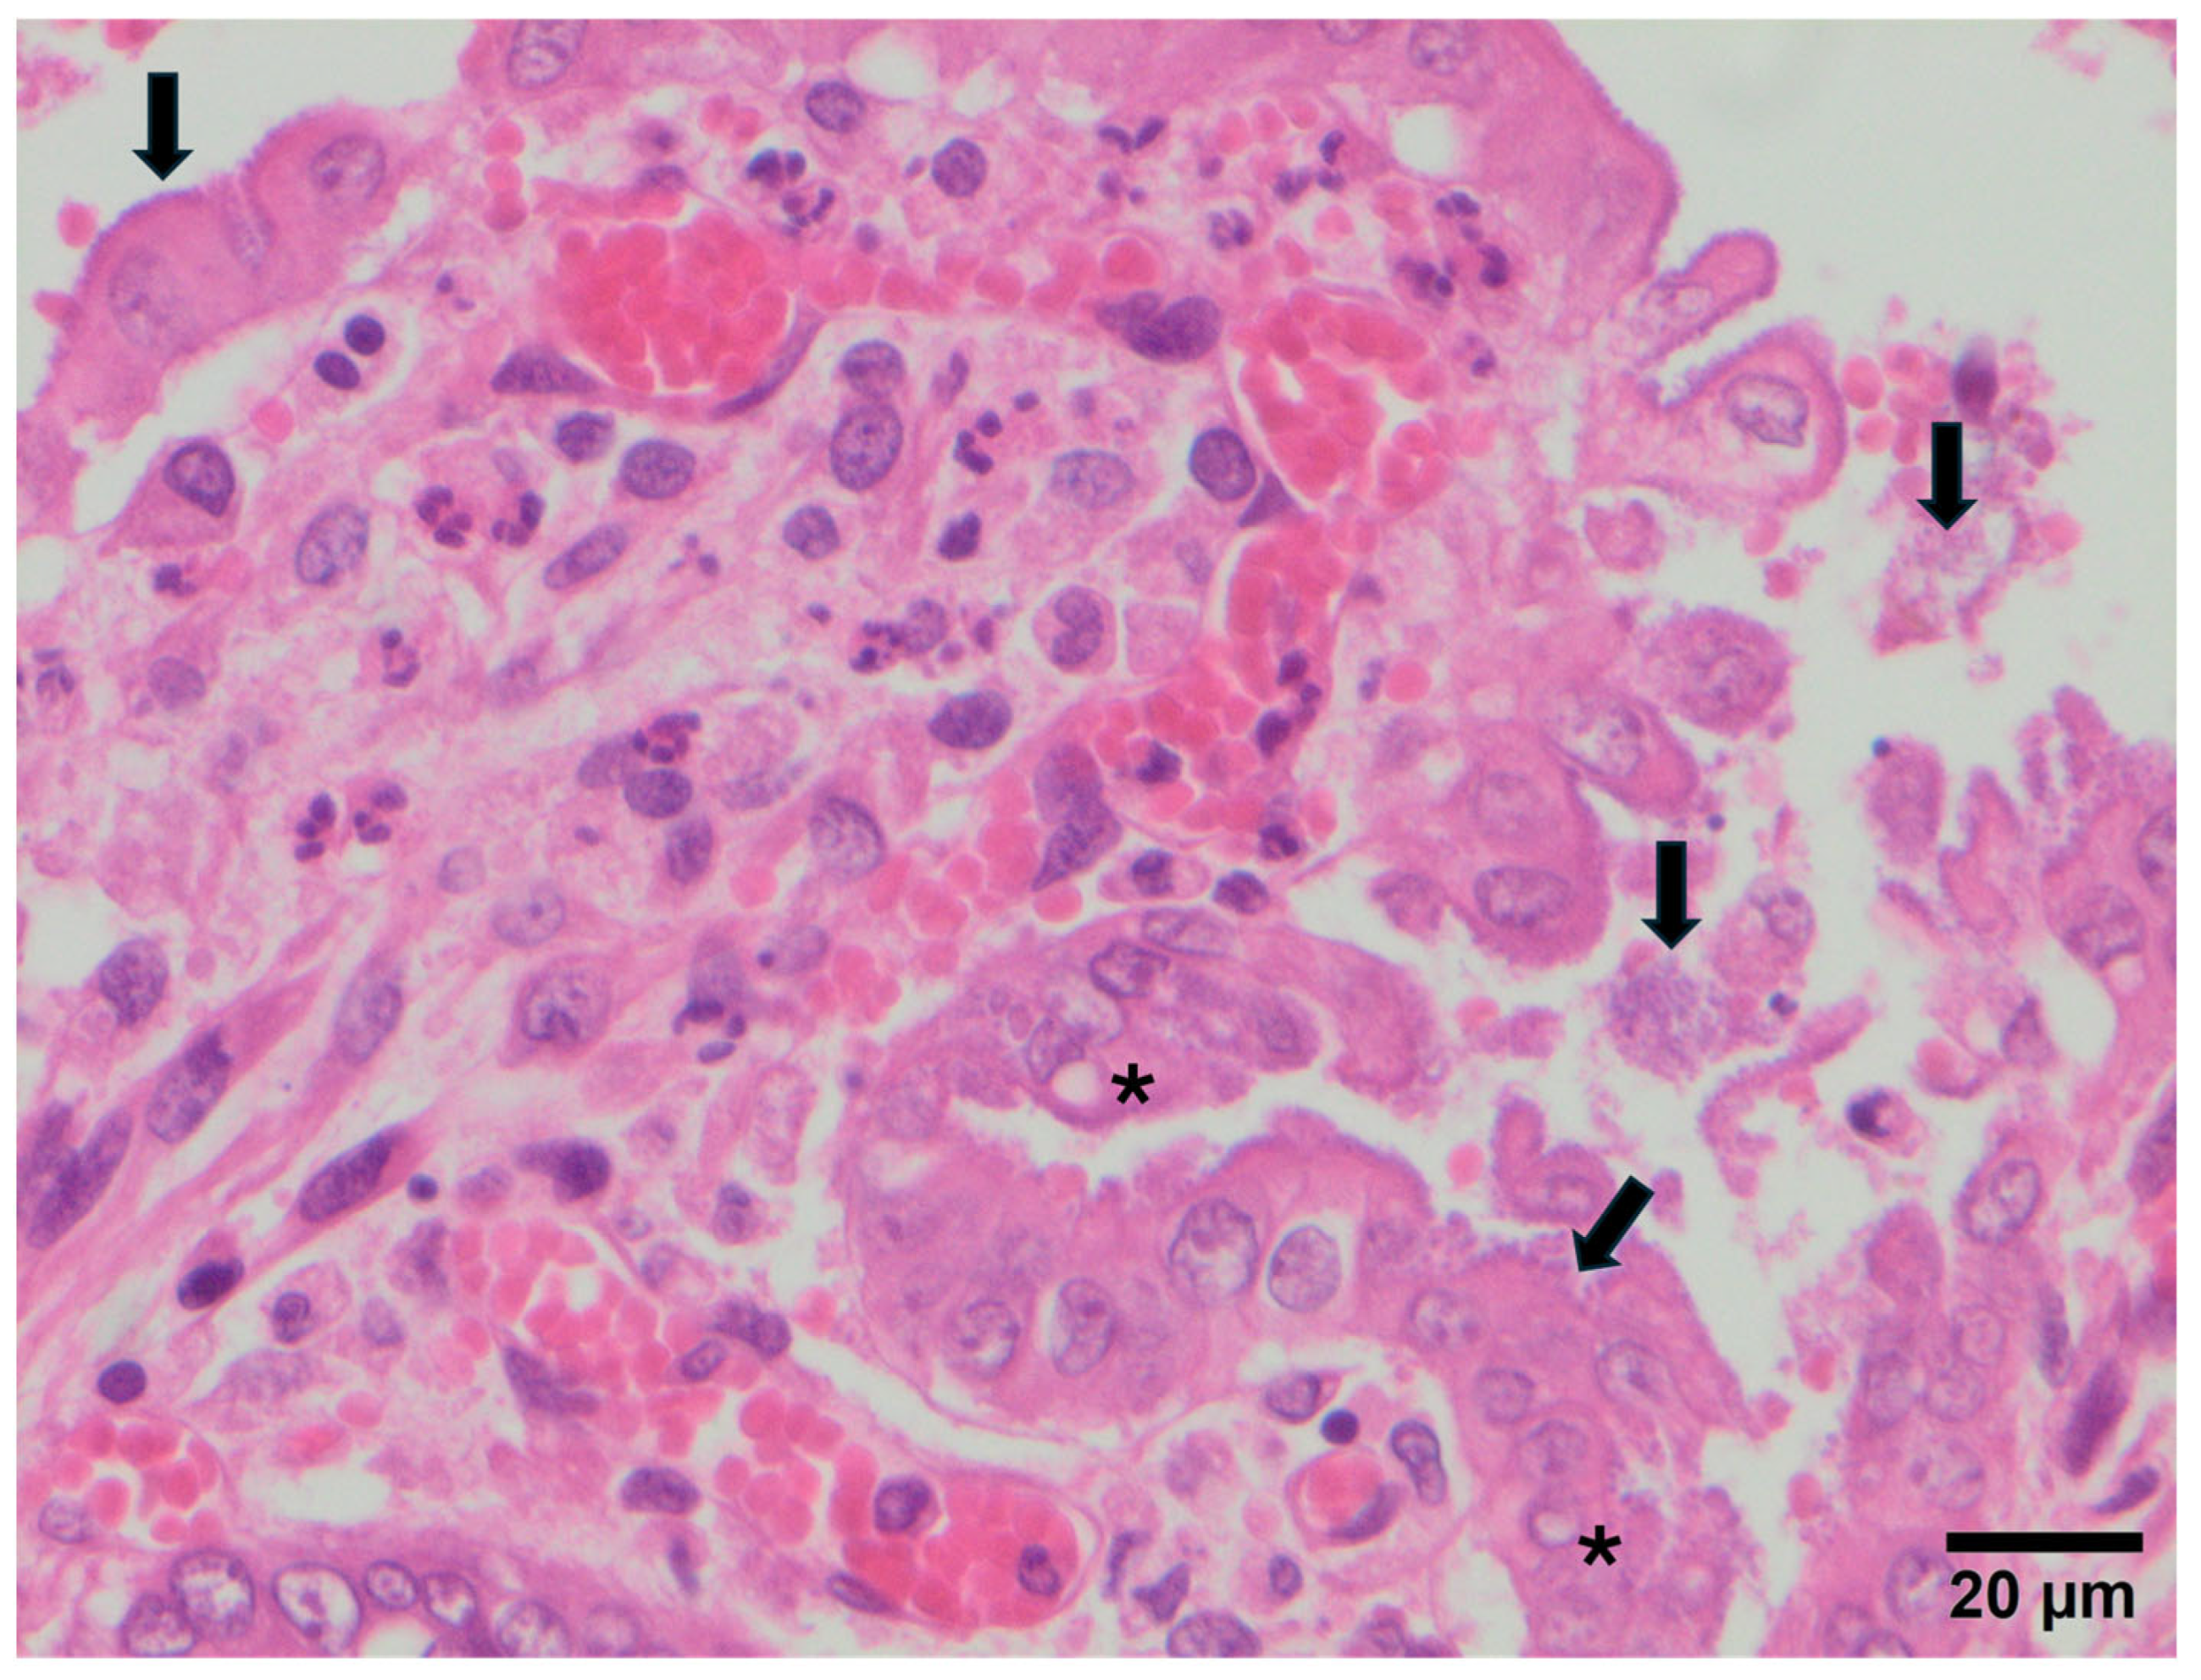

3.2. Study B: Lesional Study